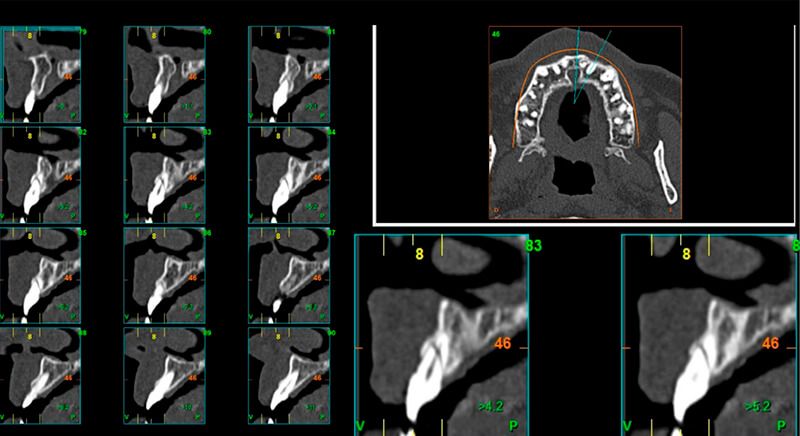

As result of an exhaustive examination a fracture of tooth 1.1 was detected, and although at first a fracture of 2.1 was not observed, it did present movement. Finally, the CT images revealed a radicular apical fracture of tooth 2.1 that meant the tooth could not be saved.

During the digital planning for the implant, with Implant Studio (3Shape) guided surgery software, significant bone defects due to the patient's anatomy were discovered. Placing the implant in the correct position for the prosthesis presented bone dehiscence in the vestibular area, and another bone defect in the palatine area due to the patient's large nasopalatine canal.

This information enabled us to rule out the option of surgery without a flap, as regeneration simultaneous to surgery would be needed, so the idea of using guided surgery was maintained.

The guided surgery was performed by lifting a full thickness mucoperiosteal flap. A Biomimetic Ocean CC implant, diameter 3.5mm and length 10mm, was inserted using the surgical guide in the ideal three-dimensional position and the defects were regenerated with xenograft and reabsorbable membrane, the nasopalatine duct on the palatine side and the area of dehiscence on the vestibular.